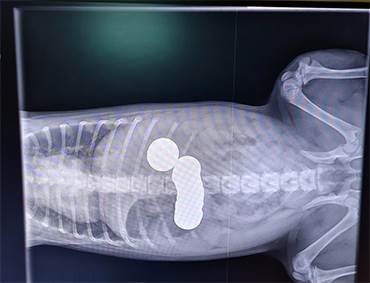

The PDSA team were stunned, as X-rays revealed a shocking number of coins in her stomach. Daisy underwent urgent surgery to remove them, while Ivana, her partner and their two children waited anxiously at home for news.

During the operation, the PDSA team removed a total of twenty coins from her stomach, including THIRTEEN 1ps, three 5ps, two 20ps and two £1 coins – swallowing a total of £2.68!

“It’s thanks to the X-rays that we were able to accurately diagnose what had happened to Daisy – they are essential for us to be able to provide vital care to poorly pets. Amazingly, across our Pet Hospitals we carry out one X-ray every two minutes but, at £135 to sedate and X-ray Daisy, they are a costly but essential part of our work. Daisy is just one example of the thousands of pets we support every year, offering them a fighting chance of survival and the ability to return home to their loving families.”